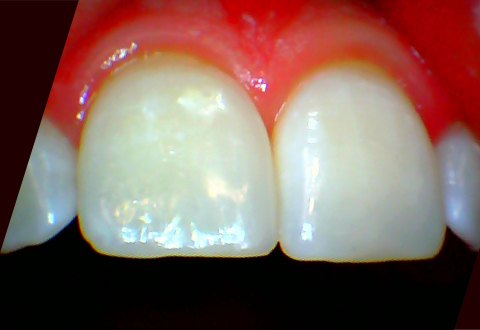

Берегите зубы, грызите орехи аккуратно! А неугодные прорехи красиво и эстетично исправят в НовДенте, сделав улыбку здоровой и готовой к любой твёрдой пище.

Пациенту была закрыта диастема и восстановлен зуб на режущем крае после произошедшего скола.

Фотография предоставлена врачом стоматологом-терапевтом – Разживиной Еленой Сергеевной